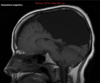

Q

35 anos, Masculino

A

Craniofaringioma adamantinomatoso

Craniofaringioma adamantinomatoso Crianças Lesão suprasselar com componente sólido e cístico; lobulado; calcificação anelar ou nodular presente em quase TODOS os craniofaringeomas pediátricos; Componente cístico proeminente e componente sólido pequeno, mas com realce.